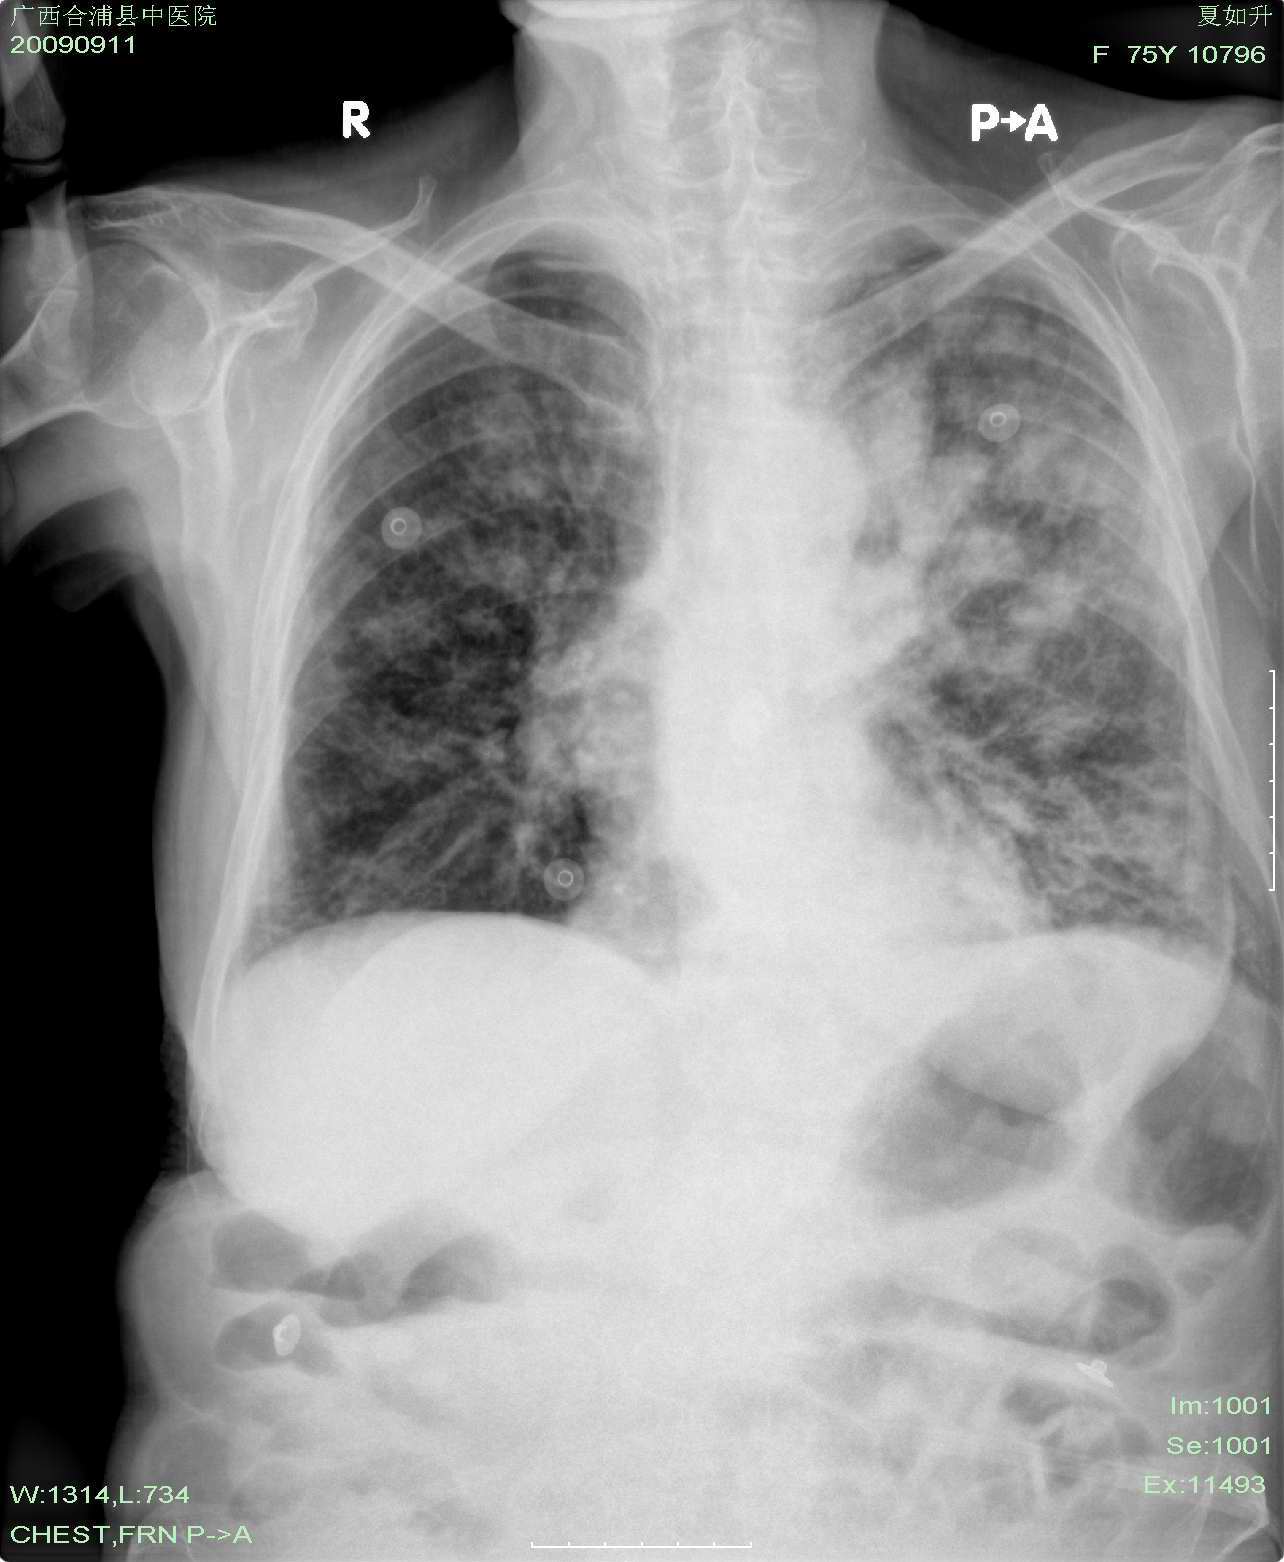

以下是引用hhx58在2009-9-11 19:48:00的发言:[br]有4个是心电监护的电极。[br]ct图片可见有肺气囊。但未拿到片上传。

以下是引用37度在2009-9-12 11:54:00的发言:[br][br] [br] 支气管扩张合并混合型感染 [br] [br]

以下是引用dyqct在2009-9-12 8:42:00的发言:[br]慢性支气管炎合并间质纤维化、肺气肿、支气管扩张、感染。建议ct进一步检查。

以下是引用黑白光影在2009-9-12 16:43:00的发言:[br]慢支并感染(霉菌?)